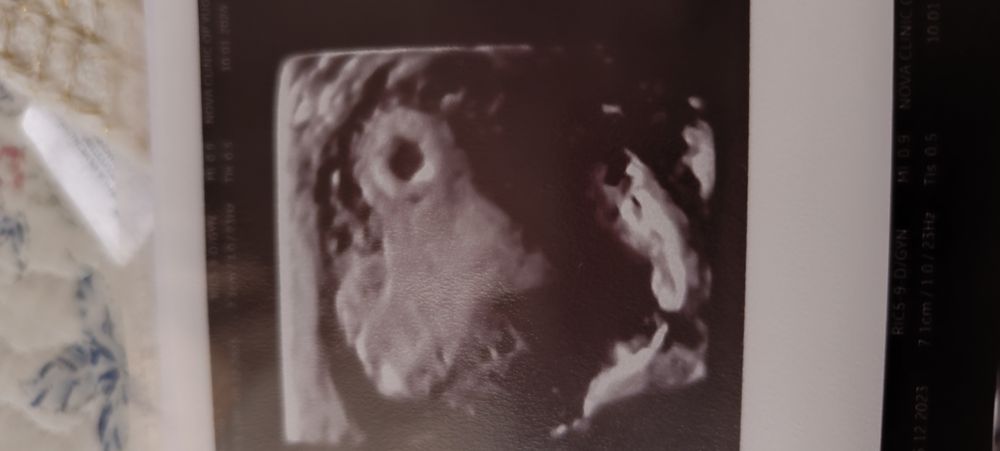

18 ДПП узи

Я БЕРЕМЕННА !Ожидала увидеть эмбрион уже, но надеюсь, что позже увидим❤💕

Вроде всё хорошо по УЗИ? Пожелайте мне удачи.

P. S. Врачу не очень понравилось место прикрепления - близко к трубе. Сказала, что должен опуститься. Не поняла это как... Если он прикрепился.